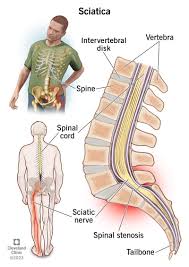

Download Sciatic nerve pain pictures